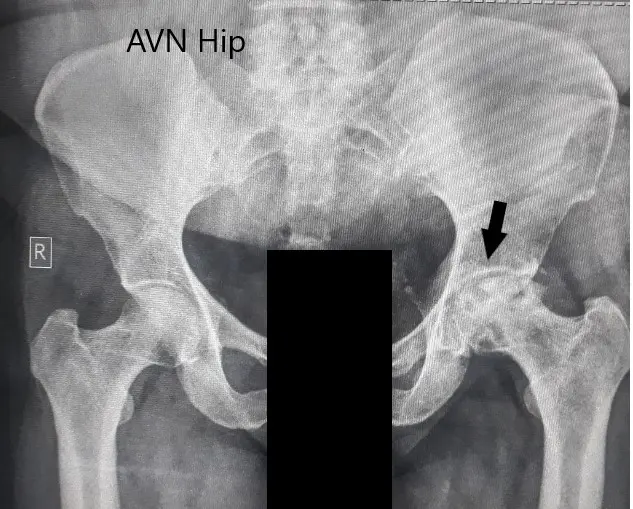

An X-Ray was obtained suggesting severe loss of joint space with acetabulum changes in the left hip. There was a loss of spherical contour of the left hip. Sclerosis and subchondral cysts were present in the left hip with a collapse.

Preoperative X-ray of the pelvis with both hips in anteroposterior view showing AVN changes in the left hip.